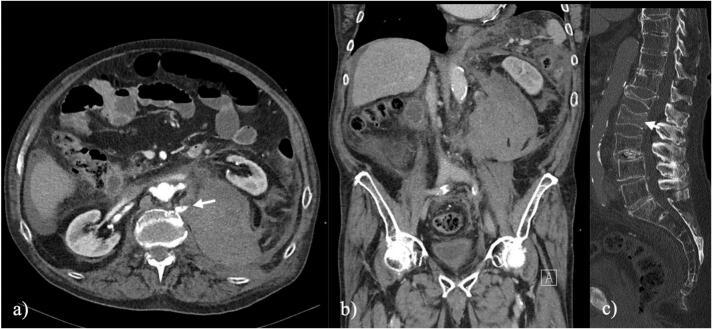

A 78-year-old male was brought to the emergency department after suffering a domestic fall with incapacitating lower back pain. X-rays and a CT scan revealed an undisplaced L2 hyperextension fracture which was treated conservatively. 9 days after admission, the patient complained about unprecedented abdominal pain with a CT scan disclosing a 12 × 9 × 20 cm retroperitoneal hematoma on grounds of an active arterial bleeding from a branch of the L2 lumbar artery. Subsequently, access via lumbotomy, evacuation of the hematoma and insertion of a hemostatic agent was performed. The therapy concept of the L2 fracture remained conservatively.

A secondary, retroperitoneal arterial bleeding after a conservatively treated undisplaced hyperextension fracture of the lumbar spine is a rare and severe complication that has not been described in literature yet and may be difficult to recognize. An early CT scan is recommended in case of a sudden onset of abdominal pain in these fractures to fasten treatment and hence decrease morbidity and mortality. Thus, this case report contributes to the awareness of this complication in a spine fracture type with increasing incidence and clinical relevance.